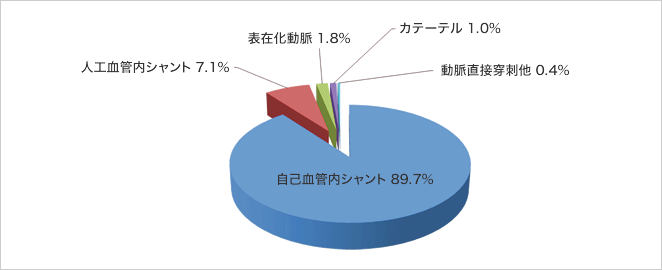

バスキュラーアクセスの種類別では、2008年統計では自己静脈内シャント90%、人工血管内シャント7%、動脈表在化2%、透析用カテーテル1%となっています。血液透析を受けておられる方の97%が内シャントでの透析であることから、バスキュラーアクセスとシャントとはほぼ同意味となっています。

バスキュラーアクセスの種類(日本透析医学会 わが国の慢性透析療法の現況 2008年)